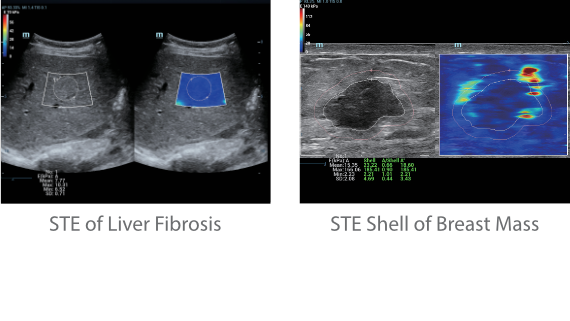

Die St?rken des Resona 7 sind bis ins kleinste Detail durchdacht. Seine erstklassige Bildqualit?t ist das Ergebnis einer erfolgreichen Fusion. Mindray und Zonare Medical Systems haben ihren Kernkompetenzen geb├╝ndelt, um ein Premiumsystem Wirklichkeit werden zu lassen. Dank der Vector Flow-Funktion k?nnen bei Gef??untersuchungen mehr als 400 Bilder pro Sekunde dargestellt werden. Somit entstehen ganz neue M?glichkeiten der Diagnose.